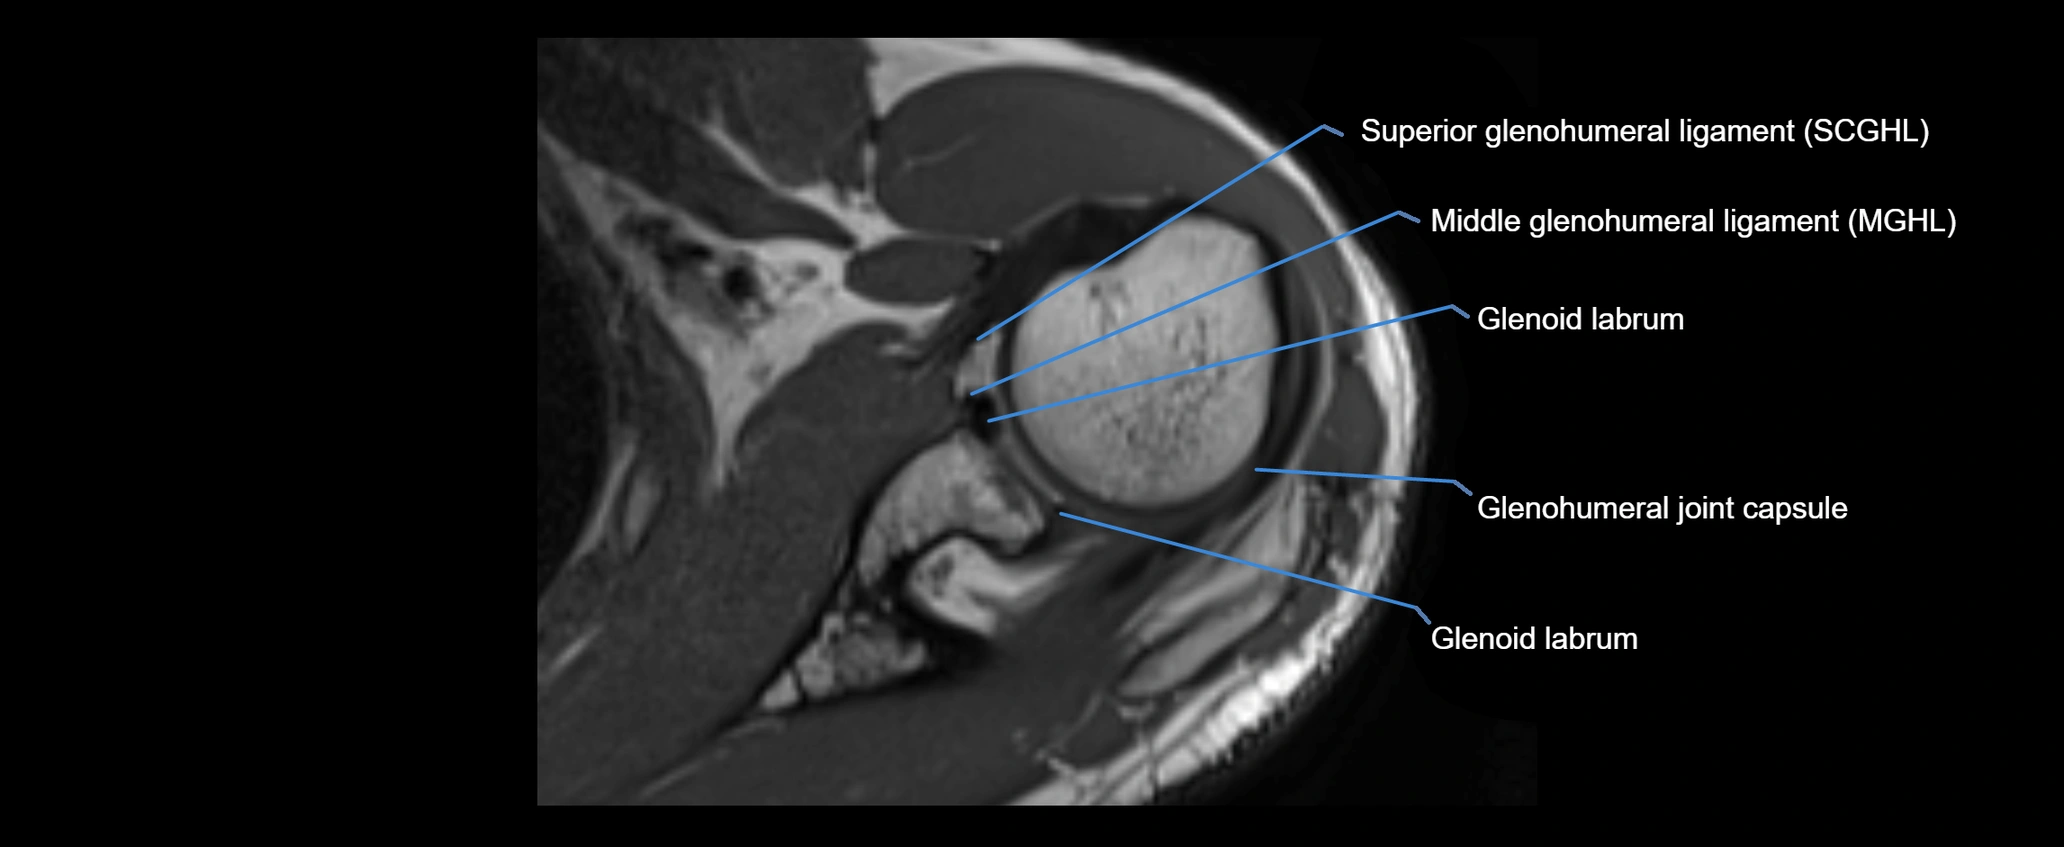

MRI images

image